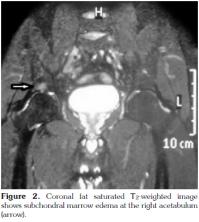

The typical MRI findings of AS are enthesisitis and ankylosis. However, at the very early stage of the disease, synovitis and and subcortical bone marrow edema are important diagnostic features. A number of studies have shown that subchondral bone marrow edema developes as a result of inflammation in various sites such as the sacroiliac joints, femoral heads, and the shoulders.[14-16] The sign of early involvement in AS is subcortical edema. Subcortical edema may be seen at the femoral head, symphisis pubis, and other sites of enthesis (Figure 1, 2). Histological studies have shown that the bone marrow edema in AS is in correlation with osteitis.[17] The femoral head bone marrow edema in AS differs from the diffuse form seen in septic arthritis, and it is more focal, frequently encountered in tendinous and ligamentous insertion sites. A similar pattern was present in the cases of our study (Figure 3). In one study, it was reported that 23% of cases with juvenile AS demonstrated subcortical edema at the symphisis pubis.[17] In our study, no bone marrow edema was encountered at the sites of the symphisis pubis of the patients. This fact may be due to the limited number of the patients enlisted in our study, and also to the difference in the patient age groups between our study and the study mentioned above.